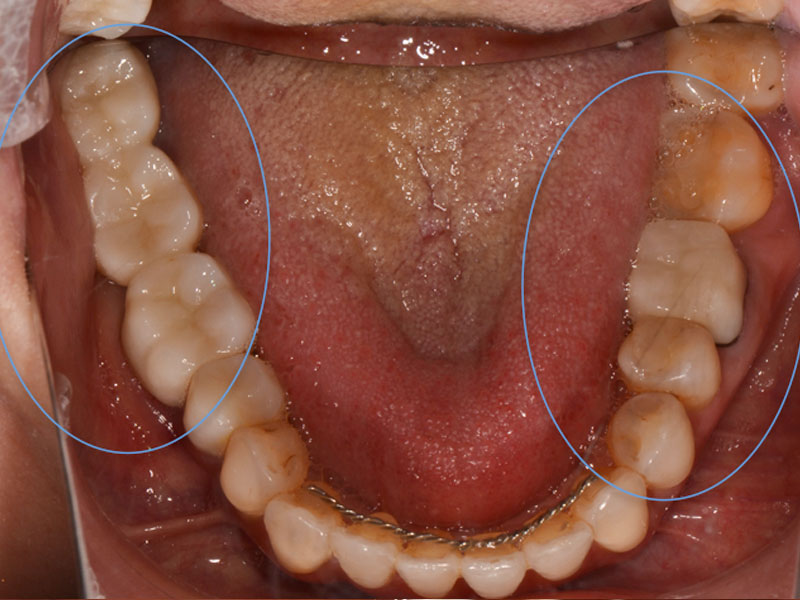

治療完了時

仮の被せ物、ものを最終的な補綴物に変更。(ジルコニアにて治療)

④ 最終補綴:3ヶ月

治療結果

初診時にあった顎の痛みは消失し、噛み合わせも安定しました。